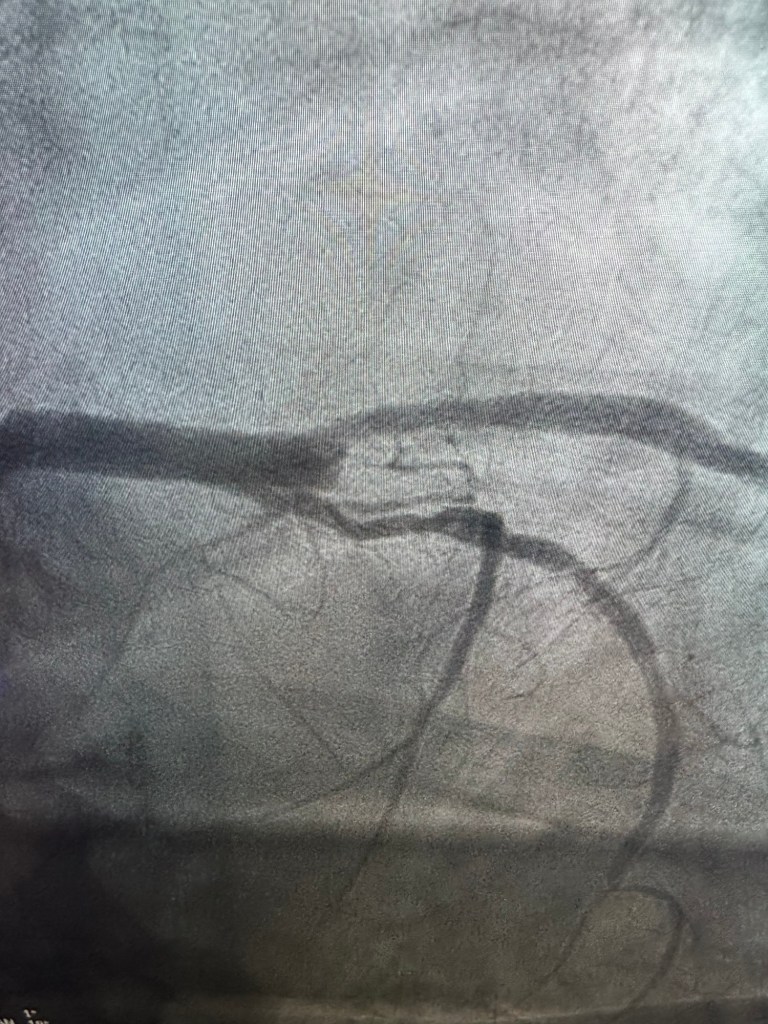

He showed me scary xrays which I still only kind of understand.

But what I do understand is that he is lucky to be alive. He had a widowmaker heart attack. There was only a 12% chance of survival and he was 90% blocked.